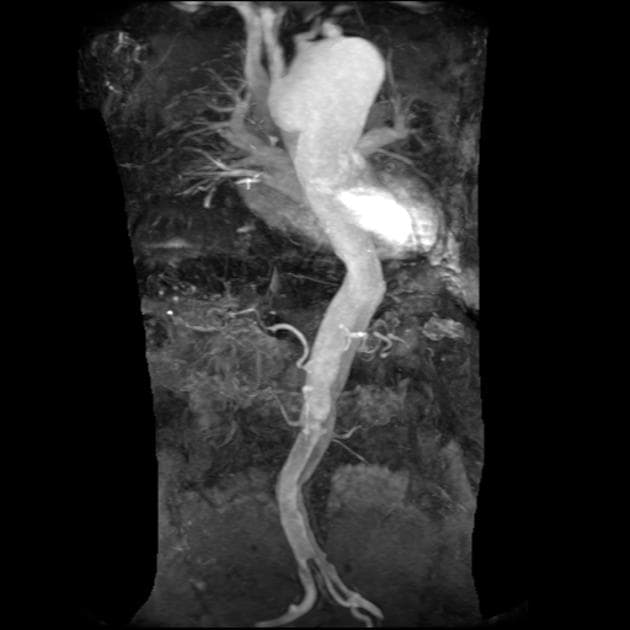

Phát hiện hình ảnh bóc tách động mạch chủ (aortic dissection) từ gốc động mạch chủ xuống đến đoạn động mạch chủ bụng gần, ngay trước khi xuất hiện các động mạch thận (renal arteries) – phù hợp với bóc tách loại Stanford A, loại DeBakey I.

Thiếu máu cục bộ tủy sống (spinal cord ischaemia) – phù hợp với biến chứng của bóc tách động mạch chủ (aortic dissection).

- "Thiếu máu cục bộ tủy sống có thể xảy ra như một biến chứng của bóc tách động mạch chủ do tắc các động mạch tủy sống quan trọng như động mạch Adamkiewicz."